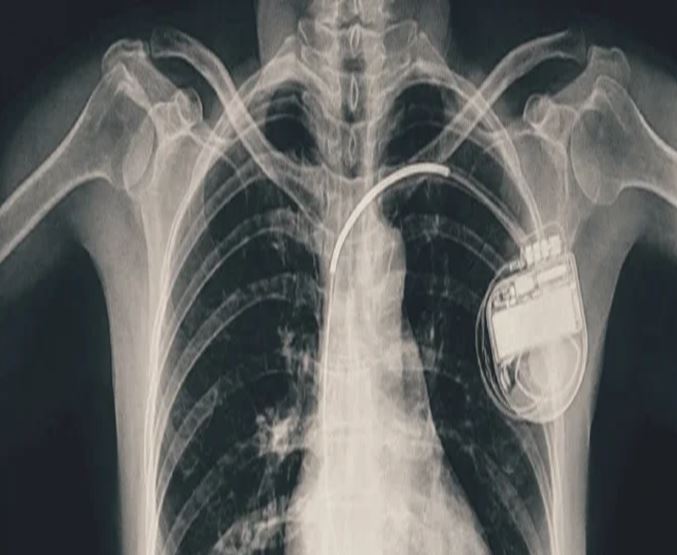

भोपाल में बच्ची के दिल की धड़कन धीमी पड़ी, डॉक्टरों ने पेसमेकर लगाकर बचाई जान

भोपाल। भोपाल मेमोरियल अस्पताल एवं अनुसंधान केंद्र (बीएमएचआरसी) के कार्डियोलॉजी विभाग ने एक दुर्लभ और चुनौतीपूर्ण चिकित्सा उपलब्धि हासिल की है। यहां 13 वर्ष की गैस पीड़ित आश्रित बालिका को इमरजेंसी में डुअल चेंबर पेसमेकर लगाकर उसकी जान बचाई गई। अब बालिका की हालत बेहतर है और उसे अस्पताल से छुट्टी दे दी गई है। यह प्रक्रिया सहायक प्रोफेसर डॉ. अमन चतुर्वेदी और उनकी टीम द्वारा सफलतापूर्वक की गई।

बीएमएचआरसी के कार्डियोलॉजी विभाग के सहायक प्रोफेसर डॉ. अमन चतुर्वेदी ने बताया कि यह मरीज जन्म से ही हृदय रोग से पीड़ित थी। तीन वर्ष की आयु में उसके दिल में छेद (congenital heart defect) का ऑपरेशन किया गया था। ऑपरेशन के बाद उसे हार्ट ब्लॉक हो गया यानी हृदय की धड़कन असामान्य रूप से धीमी हो गई। इसके कारण उसे चक्कर आना, आंखों के सामने अंधेरा छा जाना जैसी परेशानियां होने लगीं।हार्ट ब्लॉक की स्थिति में, बचपन में ही उसे एपिकार्डियल पेसिंग (epicardial pacing) डिवाइस लगाई गई। इस प्रक्रिया में पेसमेकर के तार हृदय की बाहरी सतह पर लगाए जाते हैं, जो आमतौर पर छोटे बच्चों में अपनाई जाती है, क्योंकि उनके हृदय का आकार छोटा होता है। इस डिवाइस की आयु लगभग 10 वर्ष होती है। डिवाइस की अवधि पूरी होने के बाद हाल ही में मरीज को फिर से वही लक्षण होने लगे। बीएमएचआरसी में जांच के बाद यह स्पष्ट हुआ कि अब उसे एक स्थायी और अधिक उन्नत पेसमेकर की आवश्यकता है। आपातकालीन स्थिति में टीम ने सफलतापूर्वक डुअल चेंबर पेसमेकर प्रत्यारोपित किया। इस जीवनरक्षक प्रक्रिया को अंजाम देने वाली टीम में कार्डियोलॉजी विभाग के सहायक प्रोफेसर डॉ. कपिलकांत त्रिपाठी, डॉ. नुपुर गोयल, मेडिकल ऑफिसर डॉ. अनुराग ठाकुर एवं अन्य सदस्य शामिल थे।

पेसमेकर एक छोटा उपकरण होता है, जो दिल की धड़कन को नियंत्रित करता है। यह दिल को सही गति से धड़कने में मदद करता है। सिंगल चेंबर पेसमेकर हार्ट के सिर्फ एक चेंबर को इलैक्ट्रिक सिग्नल देता है, जबकि डुअल चेंबर पेसमेकर दिल के दो भागों-ऊपरी (एट्रियम) और निचले (वेन्ट्रिकल) चेंबरों को दोनों को सिग्नल भेजता है, जिससे दिल की धड़कन और भी प्राकृतिक तरीके से चलती है। बच्ची के मामले में डुअल चेंबर पेसमेकर इसलिए लगाया गया क्योंकि उसकी स्थिति अधिक जटिल थी और बेहतर तालमेल के लिए दोनों चेंबर तक एकसाथ सिग्नल देना ज़रूरी था।